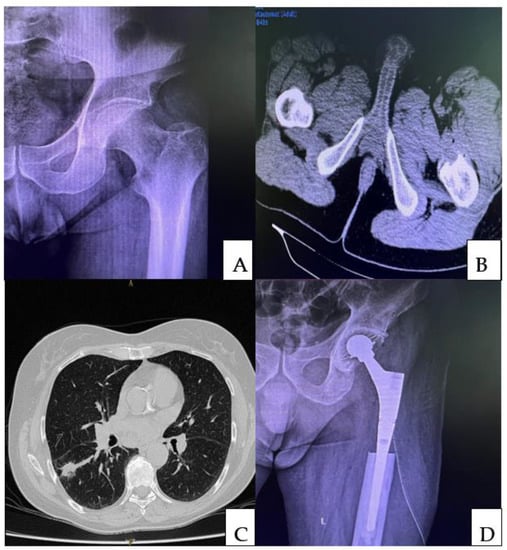

5.1. Surgical Treatment Indications and Techniques Used in Single Bone Metastases Associated with Lung Cancer

5.2. Resection and Reconstruction of Solitary Bone Lesions in Lung Cancer

5.3. Treatment of Complete or Impending Fractures in Unique Bone Metastasis following Lung Cancer—Resection Followed by Intramedullary Nails and Acrylic Bone Cement